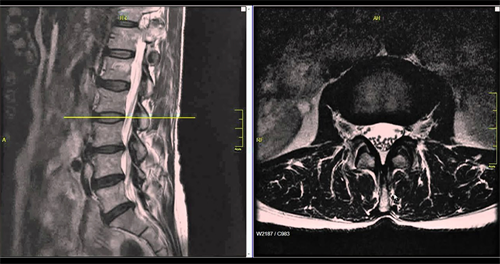

外科手术,作为椎间盘突出症的最后治疗手段并不总是解决问题的最佳方法。其实,任何椎间盘突出切除术都会对椎间盘和邻近的部分组织造成难以避免的创伤。特别是病状还没有发展到一定要做手术的状况。在这种情况下,手术的破坏程度往往要超过病状带来的危害。椎间孔镜微创手术也不列外,要摘除椎间盘突出来的部分,纤维环内肯定会留下一个相当大的窟窿,而连纤维环内最微小的裂隙都有可能引起椎间免疫反应和炎症,所谓的盘渗漏综合症。那么,保守治疗无效而症状已经无法忍受的情况下,还有什么选择呢?有没有更合理的治疗方法来解除腰病人士的痛苦?美国脊柱外科医生Dr. Kevin Pauza也同样思考过这些问题,最终研发出了Discseel®Procedure・DST椎间盘修复再生术。

Discseel®Procedure・DST椎间盘修复再生术是由美国脊椎外科医生及其团队研发的,自2010年开始应用于临床手术治疗。截止到2023年6月,已经治疗了8000余病例。目前,在亚洲地区,只有日本的野中腰椎医院拥有官方授权。Discseel® Procedure・DST椎间盘修复再生治疗与外科手术不同,不用进行开刀,只需通过0.8mm的穿刺针插入椎间盘,注射生理制剂。注入的生理制剂不仅能够修补受损的纤维环,阻止髓核流出,还能促进盘内组织再生,使椎间盘恢复一定的弹性,从根本上治疗椎间盘,达到缓解症状的目的。Discseel®Procedure・DST椎间盘修复再生术可当天出院,而且适用于其他手术失败或复发的患者,甚至适合80多岁高龄的患者。此外,DST椎间盘修复再生疗法的复发率低,有效率高达70%以上。

由于椎间盘的问题不是在一两天之内形成的,从最初充满水分、有弹性的状态,到病变为呈黑色、缺乏水分,再到纤维环破裂、椎间盘突出,需要经历一段时间。除了年龄和意外受伤外,不良的生活习惯和缺乏运动或不正确的运动是导致椎间盘长时间耗损和逐渐病变的两大原因。因此,在进行DST修复治疗后,如果肌肉仍处于僵硬、紧张、无力的状态,生活习惯仍然不佳,那么在相同的身体条件和环境下,椎间盘很可能会再次出问题。所以,在接受DST治疗后,大家必须要主动参与,从改善不良生活习惯开始,比如避免长时间坐着、长时间站立和经常提拿重物,常弯腰扭腰等。